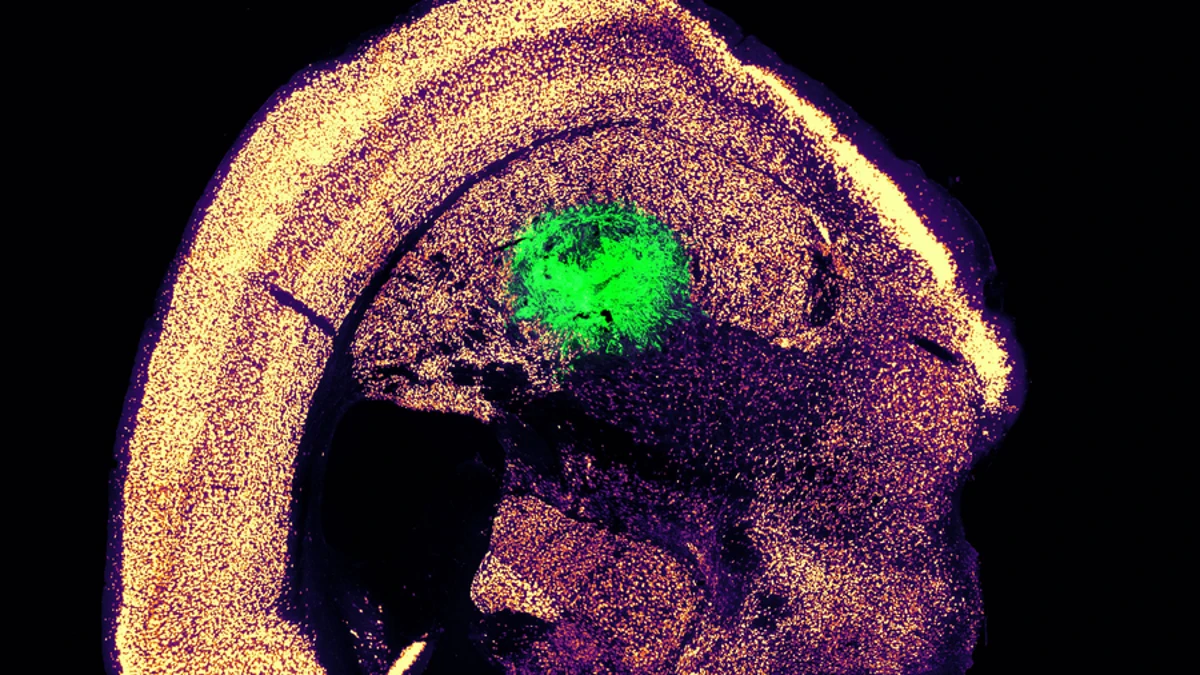

Como primer paso hacia el desarrollo y uso de estas células como terapia, Galloway demostró que podía generar neuronas motoras e injertarlas en el cerebro de ratones, donde se integraron con el tejido del huésped. Este nuevo método se describe en dos estudios publicados en Cell Systems.